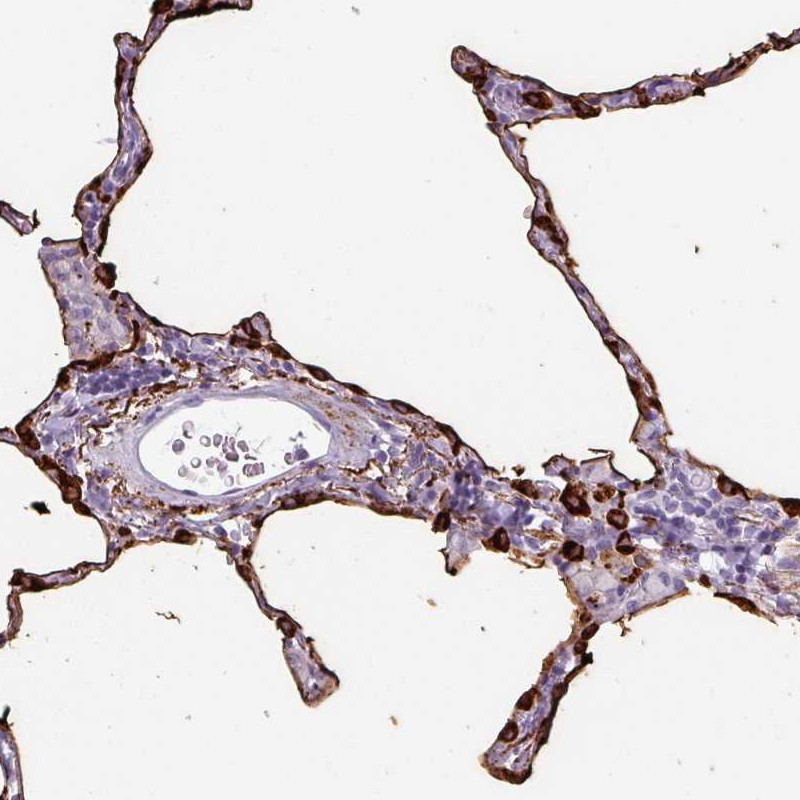

Immunohistochemical staining of human lung shows strong cytoplasmic and membranous positivity in pneumocytes.